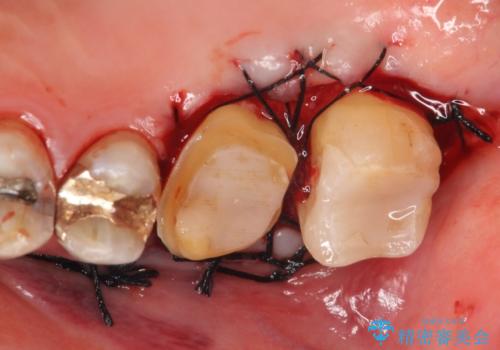

- 冷たいものがしみる右上の奥歯を治療して欲しいといらっしゃった方の症例です。

右上6,7の金歯を外したところ、虫歯が歯茎より深い位置まで進行していたため歯周外科を行いました。

その後歯茎の回復を待ち、オールセラミッククラウンおよびセラミックインレーによる補綴・修復を行いました。